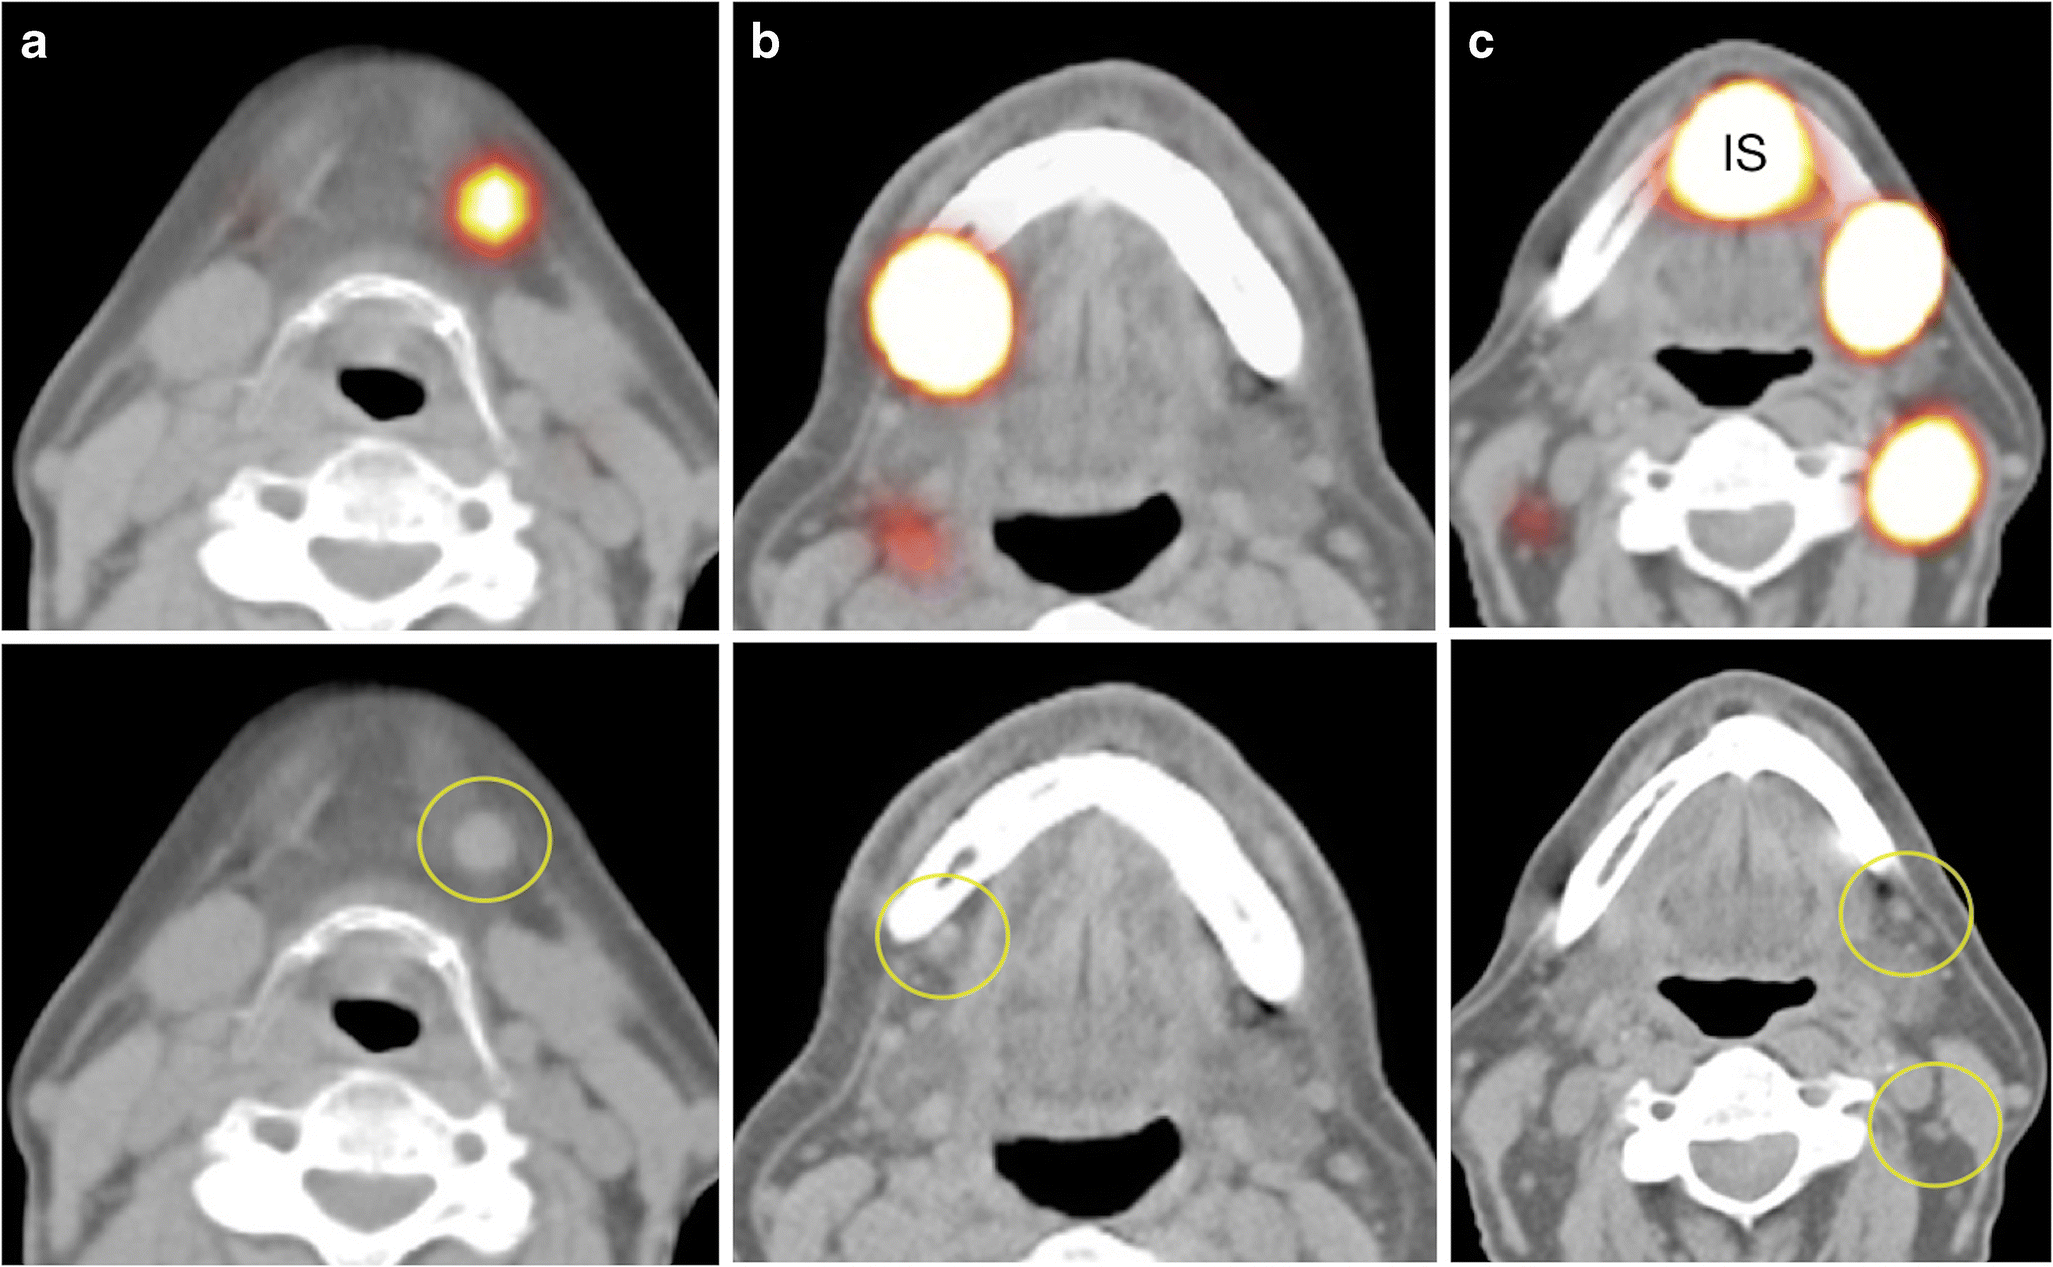

Sentinel lymph node biopsy has been very well established for melanoma and breast cancer treatment.

Lymph nodes are located all over the body and the nodes that are most easily palpated the other important lymph nodes are situated in the chest (mediastinal), abdomen. Invasion of the tumor into areas of the vertebrae. A lymph node dissection is done to: Symptoms of lung cancer may be related to the local effects of the tumor in the lung or spread of disease beyond the chest.